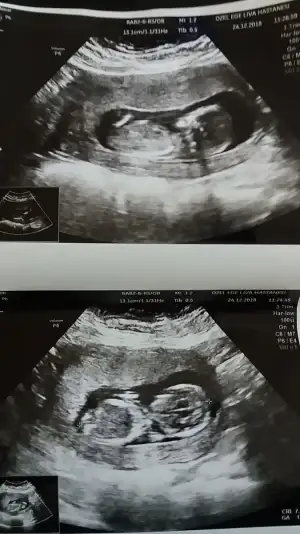

Hanimlar 13+6 dr um cinsiyet belli değil dedi kızlar belli etmez kız mı diye sordum öyle bir şey diyemem dedi bacak arası açık gibi tahmini olan var mi